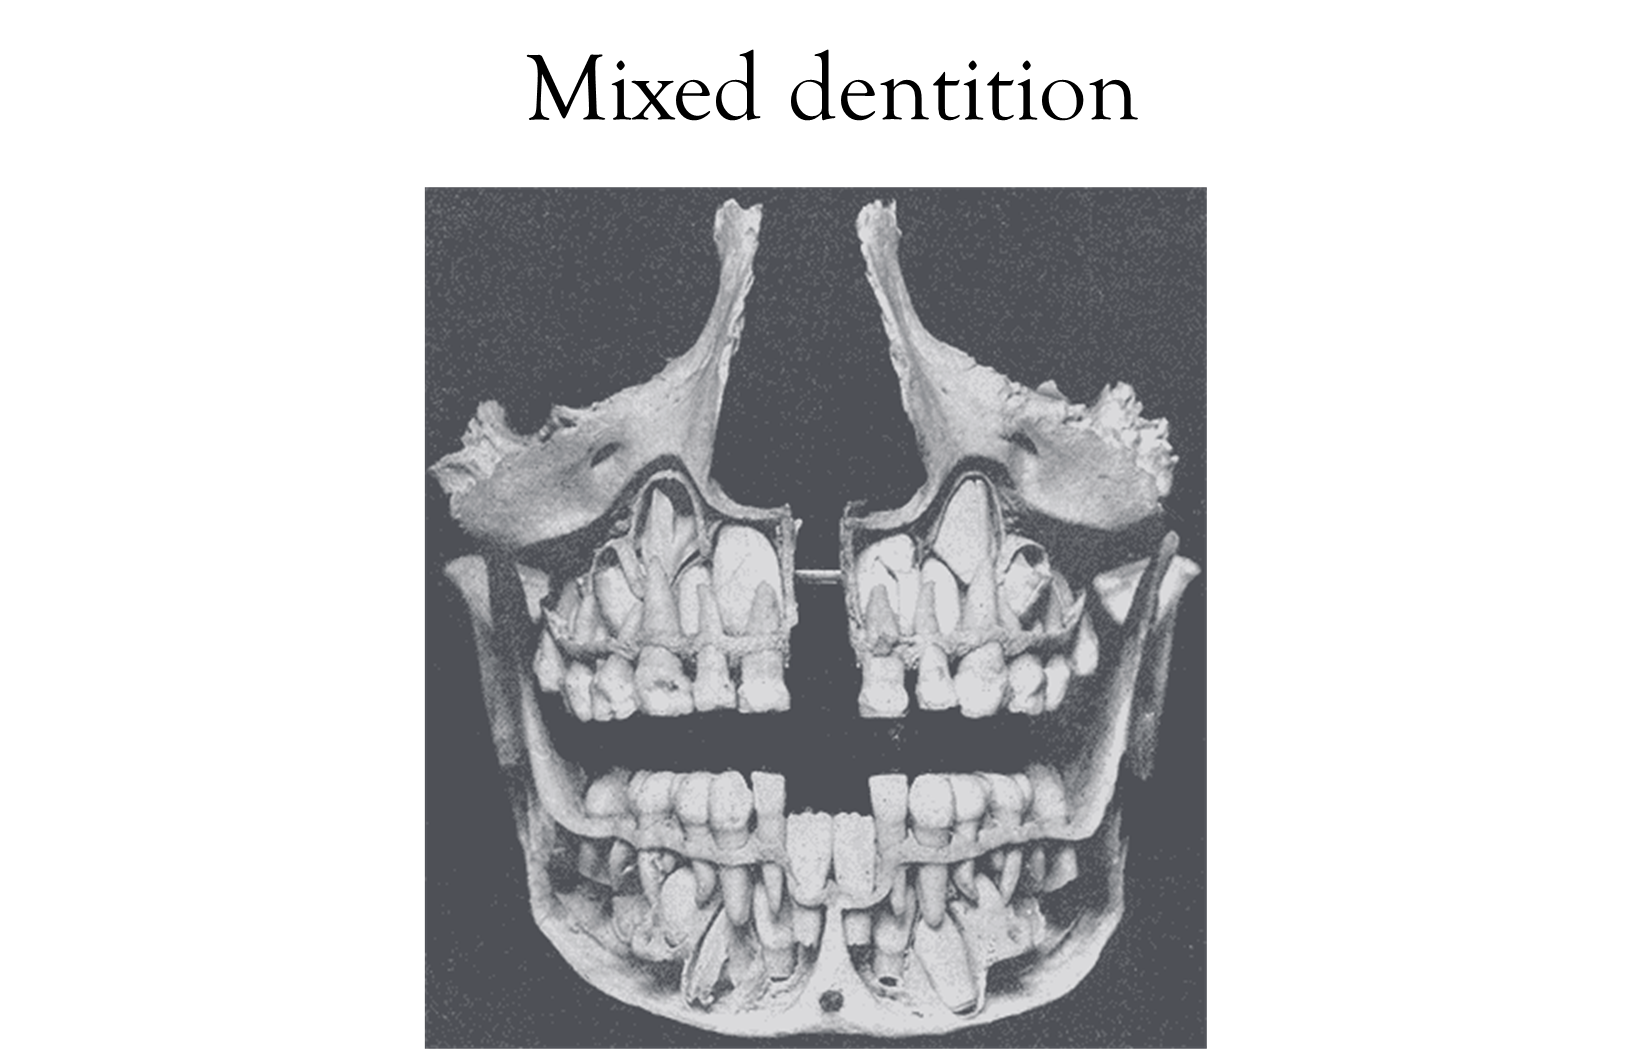

Mixed Dentition

It can be seen from ages 6 years ± 9 months to ages 12 years ± 6 months

Primary teeth come out, and permanent teeth are moving in during this time

There is a wide variance in the age of the mixed dentition stage.

This stage is significant for monitoring dental health and ensuring proper alignment as the jaws and teeth develop. Additionally, it's crucial for parents and caregivers to encourage good oral hygiene practices during this transitional period.

6.5 – 12.5 years = mixed dentition (primary shedding as permanent erupt)